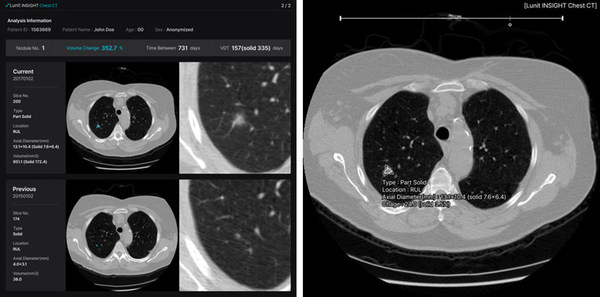

루닛 인사이트 체스트 CT는 흉부 CT 영상에서 검출된 결절의 위치, 유형, 부피, 크기 등을 3차원으로 자동 생성하는 솔루션이다. 루닛 인사이트 DBT는 AI를 활용해 병변이 의심되는 3차원 영상 이미지를 빠른 속도로 표시하는 솔루션이다. 이들 신제품은 기존 2차원(2D) 영상 진단에서 3차원(3D)으로 제품군이 확장됐다는 점에서 의미가 크다.